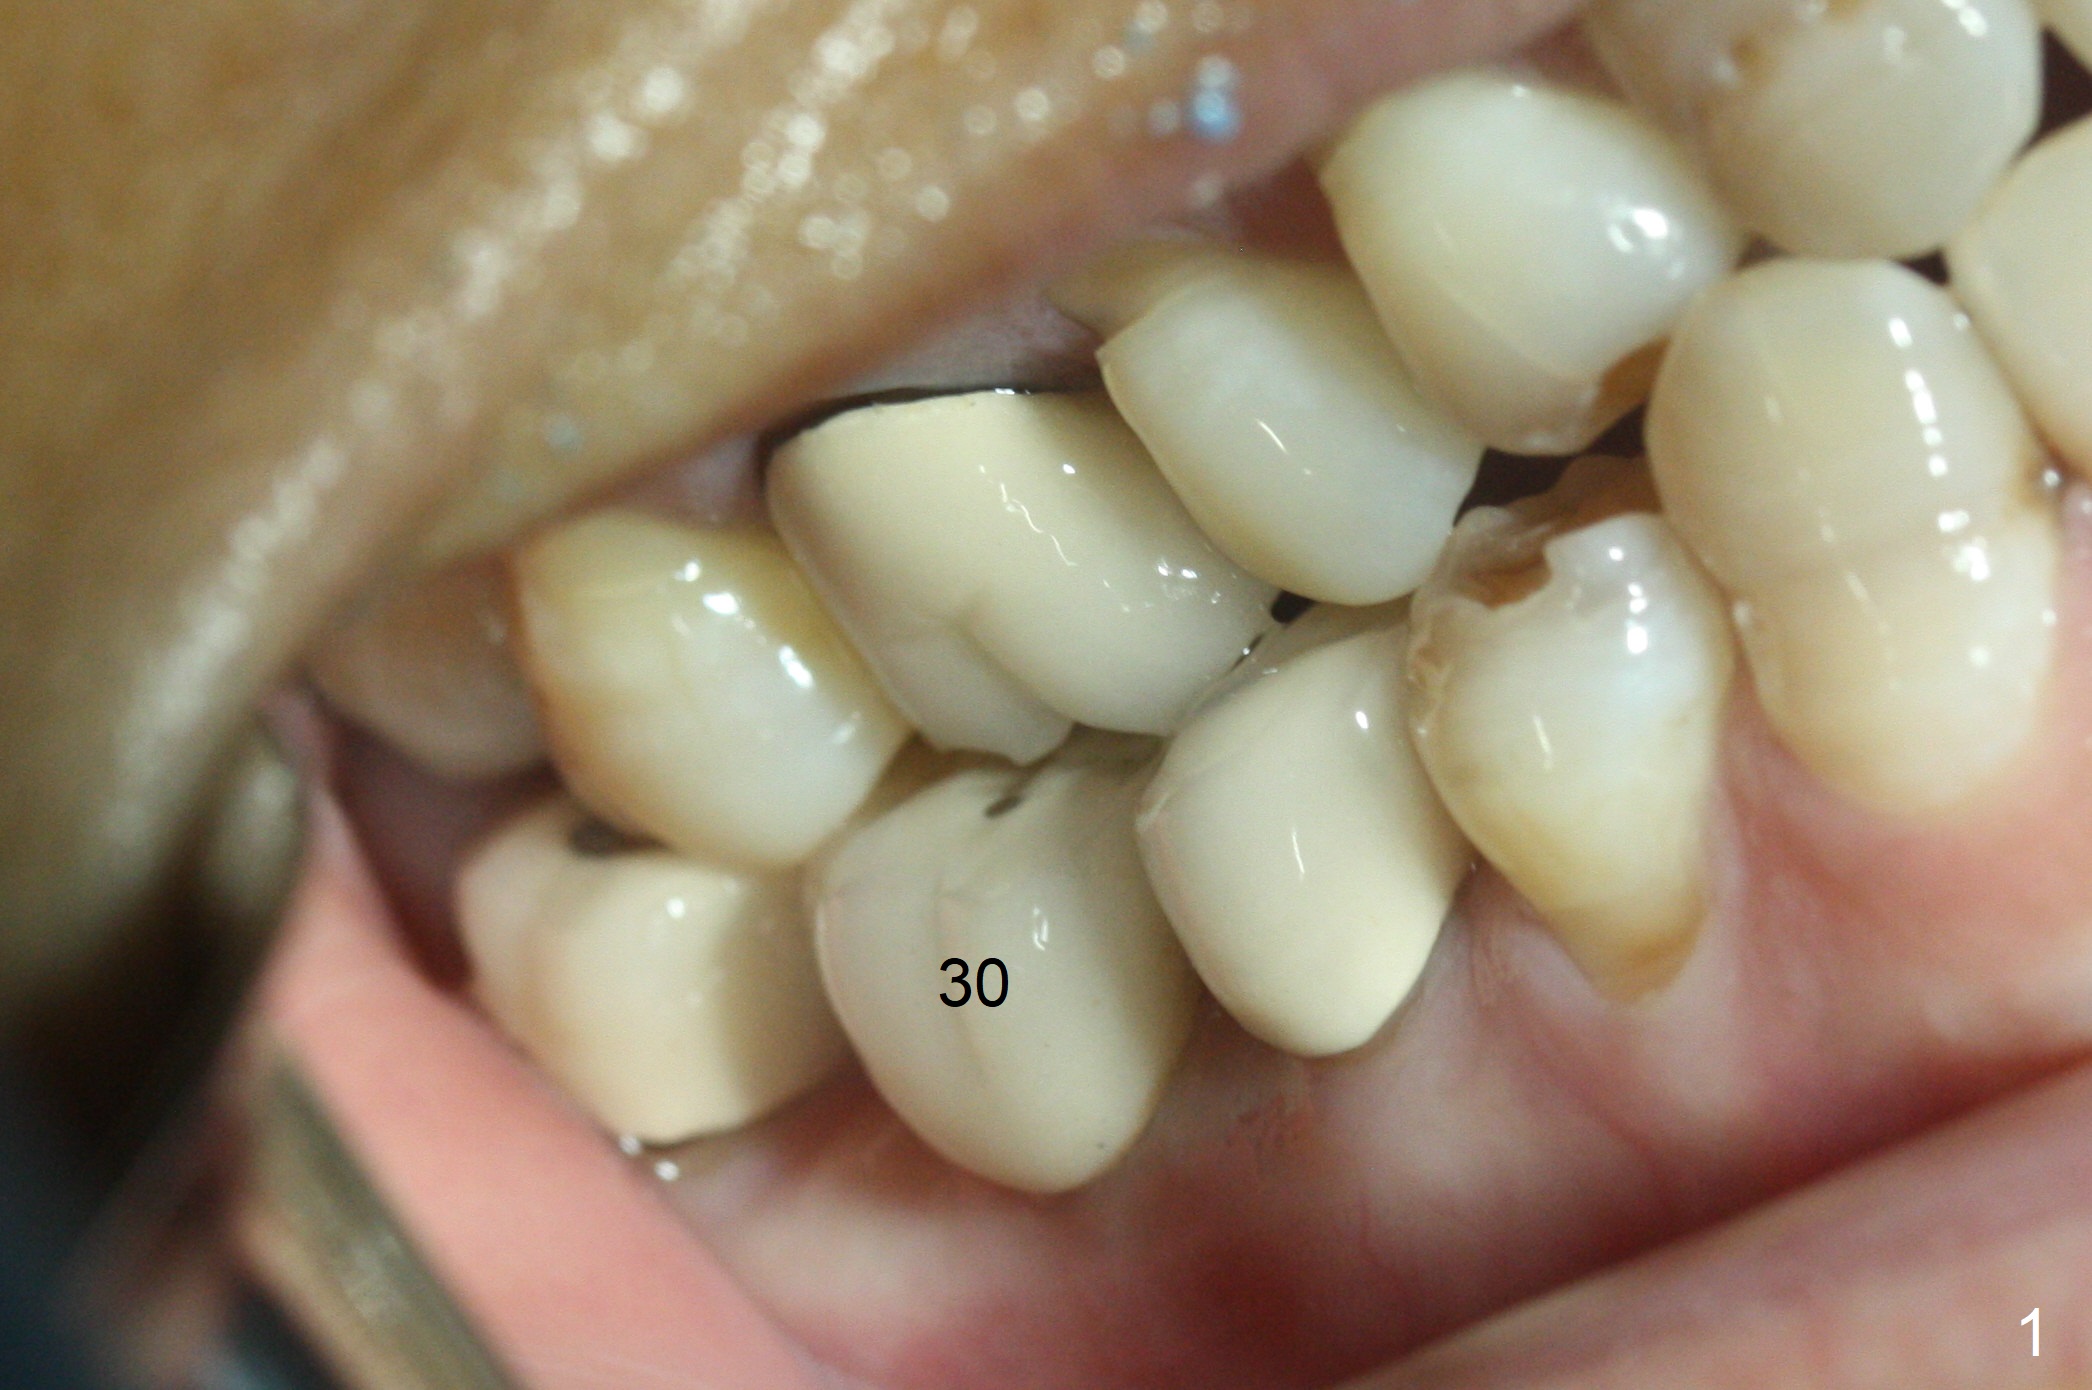

The apparently narrow ridge at #30 before bridge sectioning (Fig.1) is confirmed with incision (Fig.2). Following ridge reduction, osteotomy is initiated with 2 mm pilot drill (Fig.3). When a 3.8x12 mm SM narrow implant is placed with 40 Ncm, there is 1-2 mm cortical bone buccolingually (Fig.4,5). The thick cortices do not seem to be easy to be bent, i.e., expanded. RCT is finished at #31 one month post implant placement (Fig.6,7), the flattened ridge appears to have started to undergo remodeling. Ridge reduction makes it possible for the implant to remain subcrestal postop (Fig.4). The bone surrounding the implant may reduce the likelihood of implant fracture. The crowns at #30 and 31will be fabricated together with light occlusion at #30. In fact the splinted provisional dislodges. There appears dense bone formation 3 months postop (Fig.8 *). The drawback of using a SM narrow implant is that a narrow abutment has to be used (4.8x4(4.5) mm). The implant crown is dislodged immediately after the patient finishes lunch. Following recementation, the occlusion is reduced. In fact, UF or IBS has no such drawback: the implant could be small, but the abutment could be large. One year post cementation, the crown at #31 needs recementation (Fig.9); the bone density next to the coronal implant increases (*).